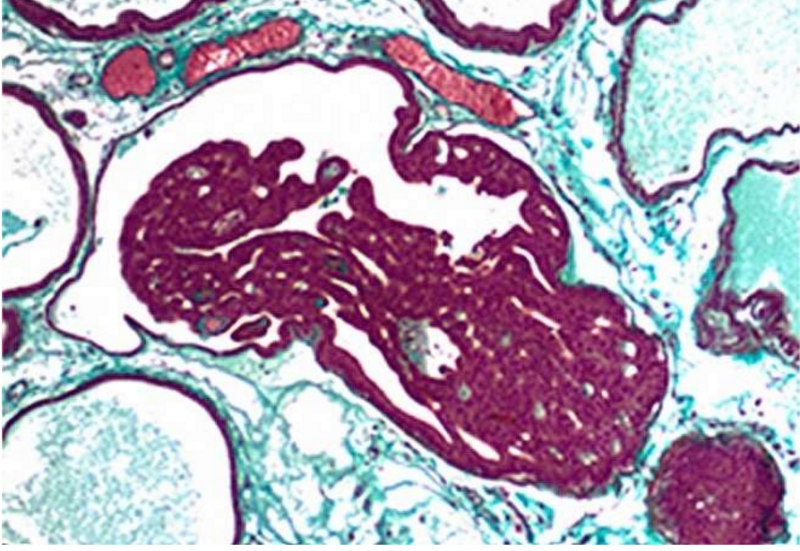

在一半以上的前列腺肿瘤中,两个基因:ERG的转录因子和TMPRSS2的睾酮触发基因融合在一起,可导致过量的ERG表达,TMPRSS2-ERG蛋白推动前列腺细胞癌变。  研究发现将称为BAF复合物对于用于启动基因表达程序至关重要,他们在正常前列腺细胞中沉默。他们发现,这一复合物可以促进前列腺细胞向癌细胞的转化,并可能为前列腺癌药物的开发提供新的机会。 像ER